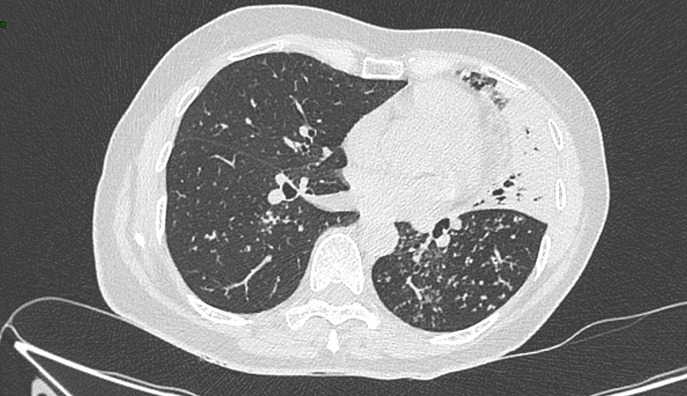

Un scanner thoracique est finalement réalisé devant cette toux chronique et l’altération de l’état général, dont voici quelques coupes :

Figure 4 (Jacques Durin, La Revue du Praticien)

Flèche bleue.

Le compte-rendu de radiologie décrit un aspect de pneumopathie lobaire supérieure gauche associée à des micronodules péri-bronchiolaires et des adénopathies médiastino-hilaires calcifiées.